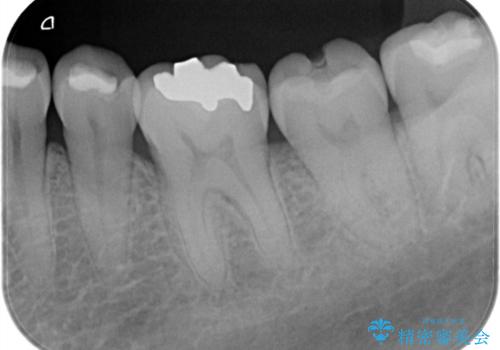

- 左下の奥歯の詰め物が取れたとのことで来院されました。診察したところ、左下6番には噛む力による複数のヒビ(クラック)が確認され、歯の寿命を考えると将来的な破折のリスクがある状態でした。

噛む力が強い方に多く見られる症状であり、これ以上の破折を防ぐためには補綴による補強が必要と判断しました。治療計画としては、左下6・7番ともに全体を覆うセラミッククラウンで補強し、咬合力に耐えられる状態に回復させる方針を立てました。また、清掃がしづらく炎症の原因にもなっていた親知らずについても、全体の予後を考えて抜歯することとしました。